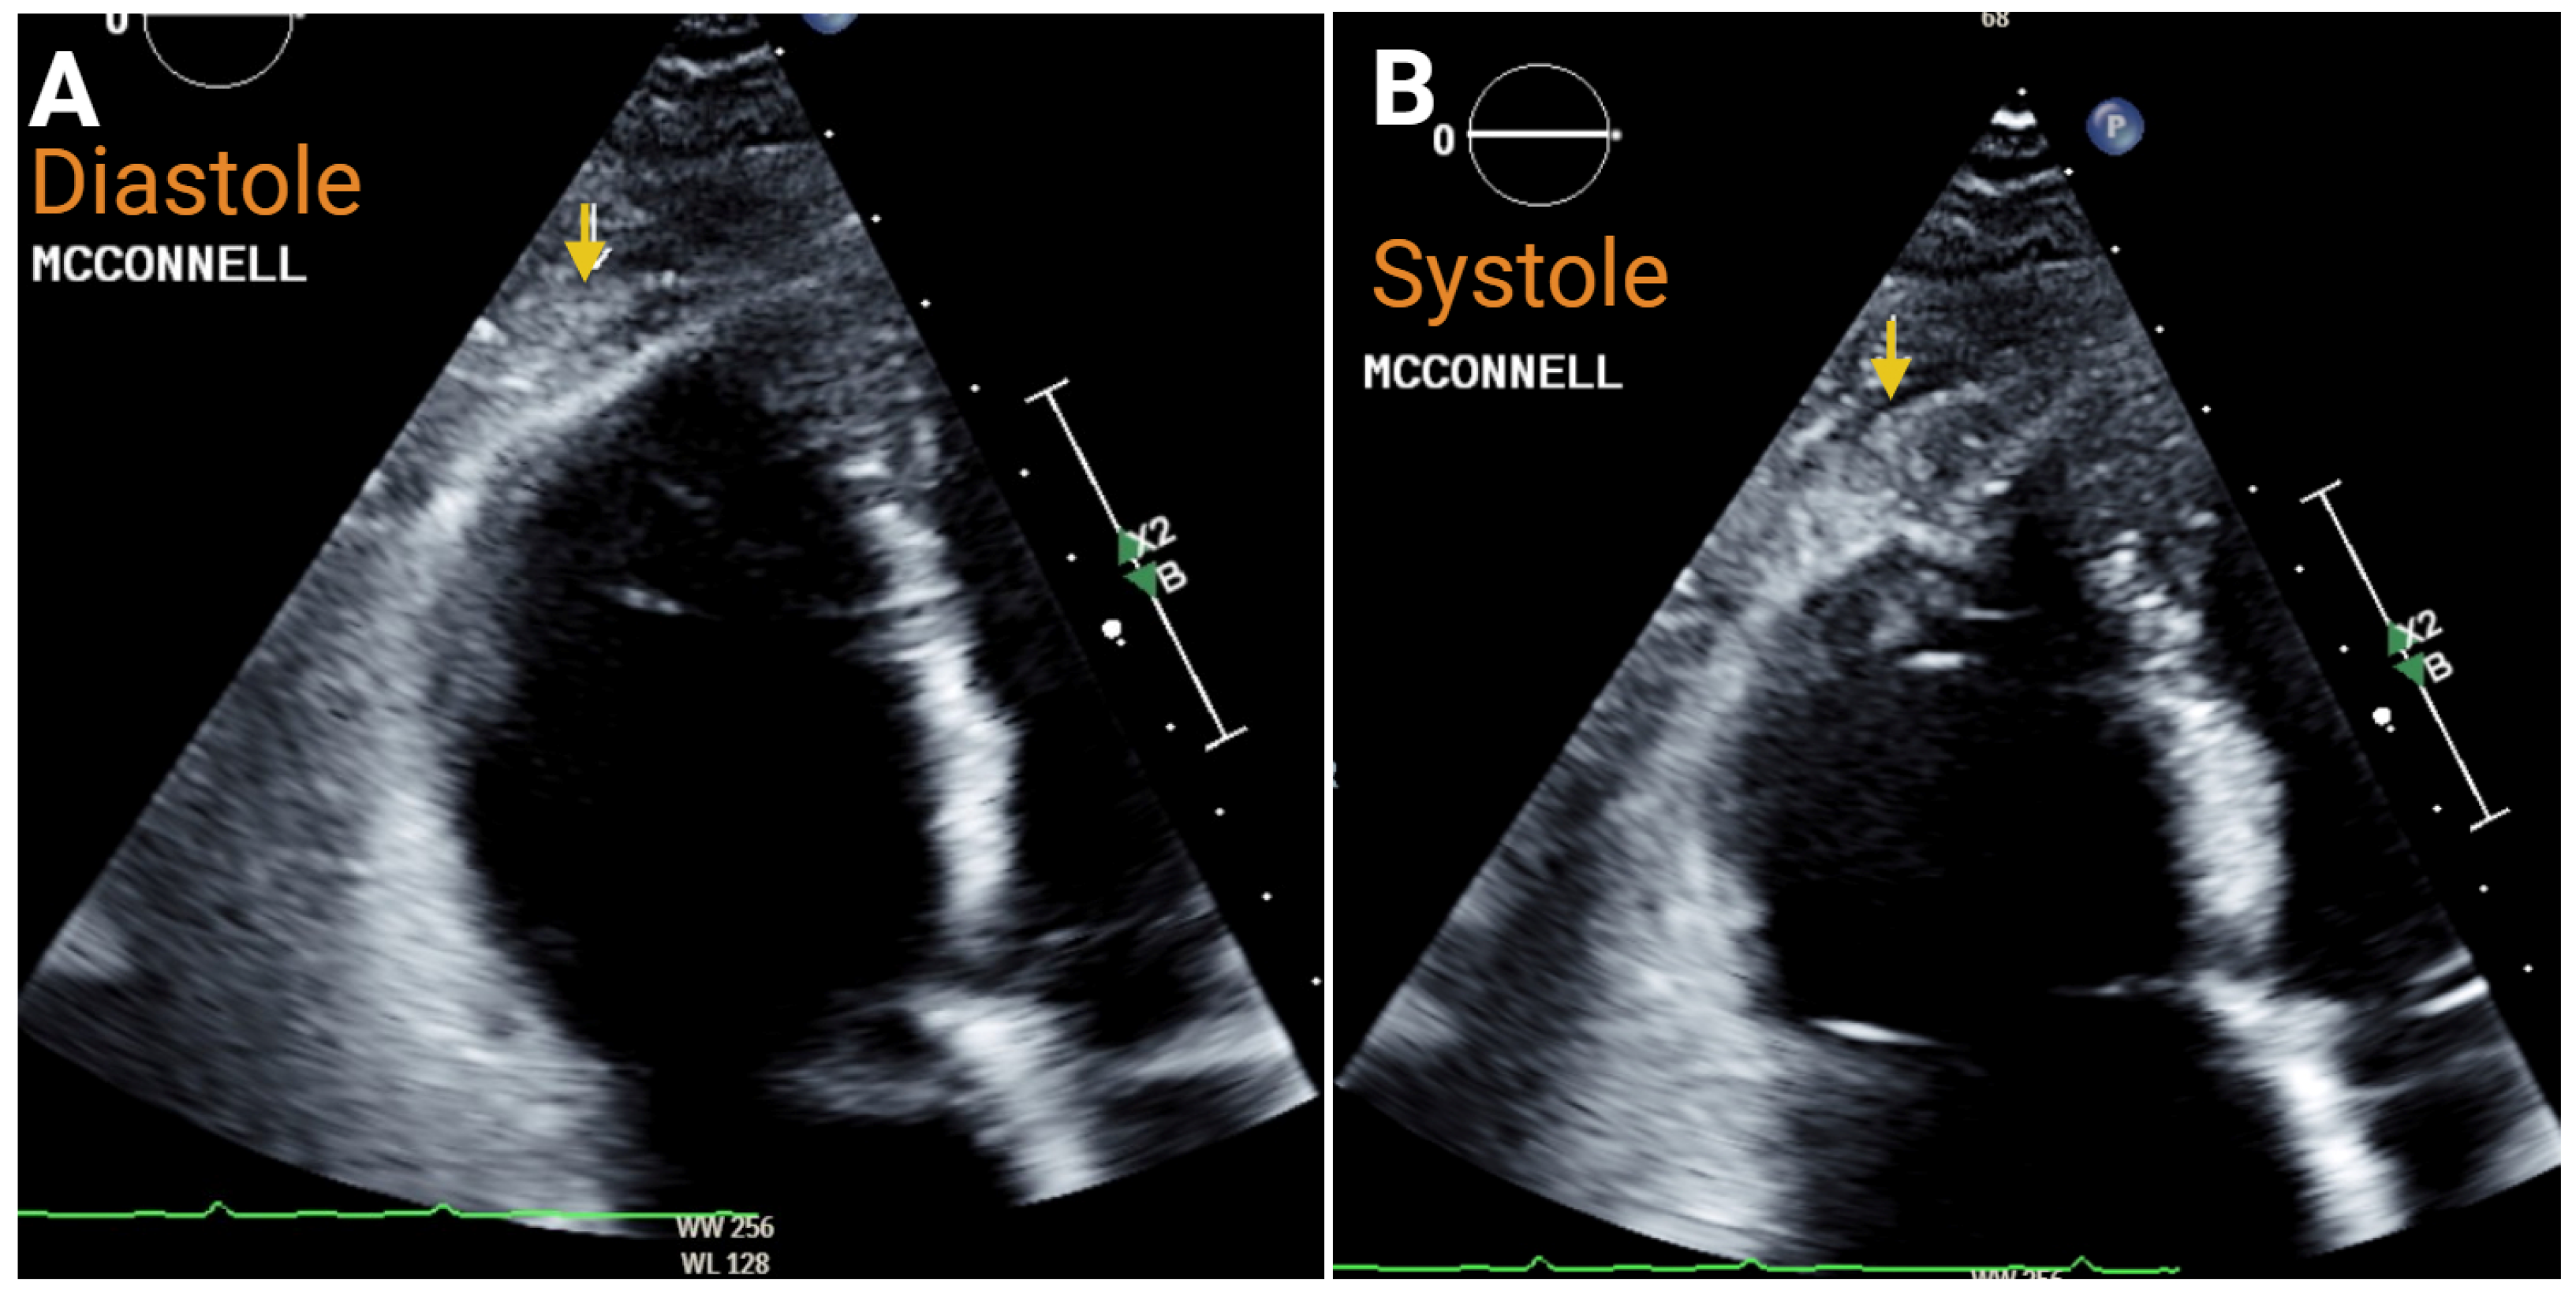

- Kurzyna, M.; Torbicki, A.; Pruszczyk, P.; Burakowska, B.; Fijalkowska, A.; Kober, J.; Oniszh, K.; Kuca, P.; Tomkowski, W.; Burakowski, J.; et al. Disturbed right ventricular ejection pattern as a new Doppler echocardiographic sign of acute pulmonary embolism. Am. J. Cardiol. 2002, 90, 507–511. [Google Scholar] [CrossRef] [PubMed]

- Kurnicka, K.; Lichodziejewska, B.; Goliszek, S.; Dzikowska-Diduch, O.; Zdonczyk, O.; Kozlowska, M.; Kostrubiec, M.; Ciurzynski, M.; Palczewski, P.; Grudzka, K.; et al. Echocardiographic Pattern of Acute Pulmonary Embolism: Analysis of 511 Consecutive Patients. J. Am. Soc. Echocardiogr. 2016, 29, 907–913. [Google Scholar] [CrossRef] [PubMed]

- McConnell, M.V.; Solomon, S.D.; Rayan, M.E.; Come, P.C.; Goldhaber, S.Z.; Lee, R.T. Regional right ventricular dysfunction detected by echocardiography in acute pulmonary embolism. Am. J. Cardiol. 1996, 78, 469–473. [Google Scholar] [CrossRef] [PubMed]